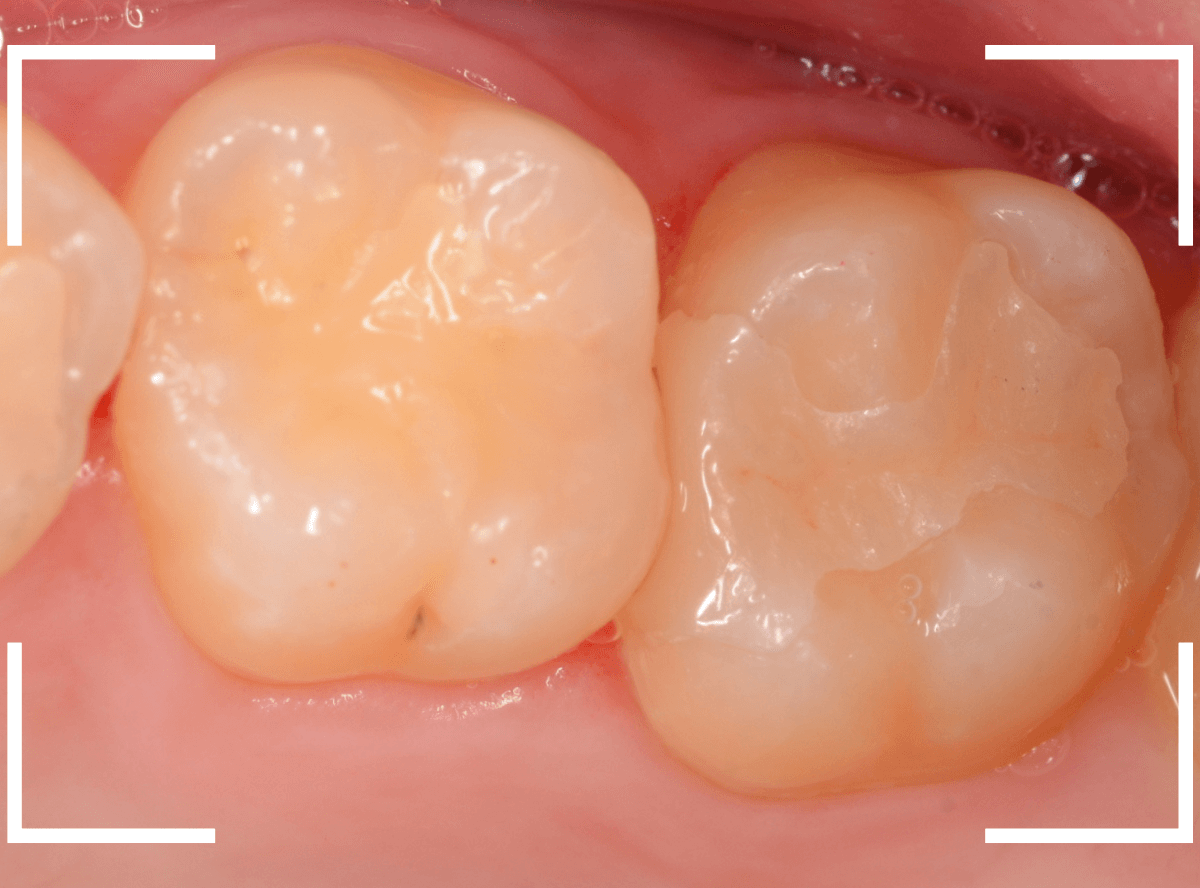

Case.30 上の奥歯のセラミック治療

メンテナンス中に、虫歯が見つかった方のケースです。

大きな虫歯でしたので、しばらく経過観察しましたが、特に症状もありませんでしたので、患者さんの希望に伴い、ジルコニア・インレーで治療をします。

治療後の状態です。

ジルコニア・インレーはE-MAX・インレーより審美性に劣るのですが、患者さんにもご満足いただける仕上がりになり、ホッとしました。